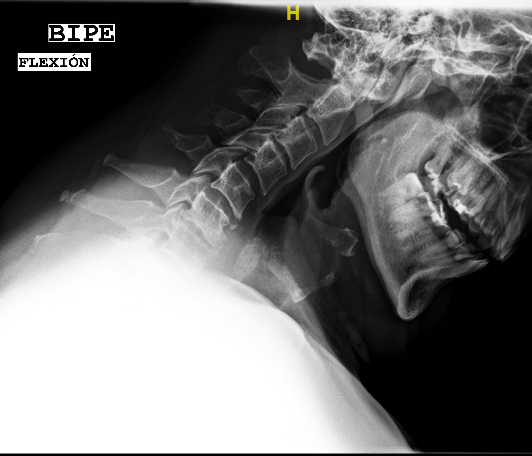

Las RX dinámicas reflejan la ausencia de fusión C6-C7